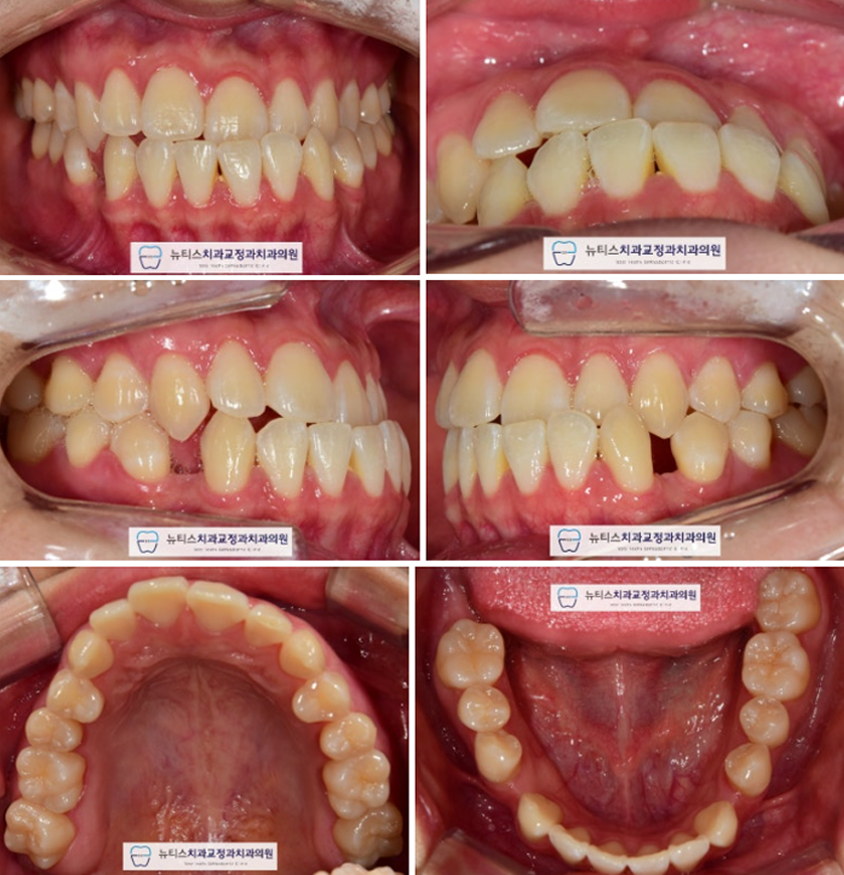

±³Á¤ ¿Ï·á ÈÄ »çÁøÀÔ´Ï´Ù.

#¹Ý´ë±³ÇÕ ÀÌ °³¼±µÇ°í

¾Æ·¡¿¡ ³²¾ÆÀÖ´Â Æ´À» ÀüºÎ ´Ý¾Ò½À´Ï´Ù.

¾Õ´Ï »Ó¸¸ ¾Æ´Ï¶ó ¾î±Ý´ÏÀÇ ±³ÇÕ±îÁö

°³¼±ÇÏ°í ¸¶¹«¸®µÇ¾ú½À´Ï´Ù.

Àü ÈÄ ºñ±³ »çÁøÀÔ´Ï´Ù.

ÃÊÁø°ú ºñ±³½Ã #¹Ý´ë±³ÇÕ ÀÌ °³¼±µÇ¾ú°í

ÇϾǿ¡ ³²¾ÆÀÖ´ø °ø°£µµ ¸ðµÎ ´ÝÇû½À´Ï´Ù.

(Ä¡·á±â°£ : 25 °³¿ù)